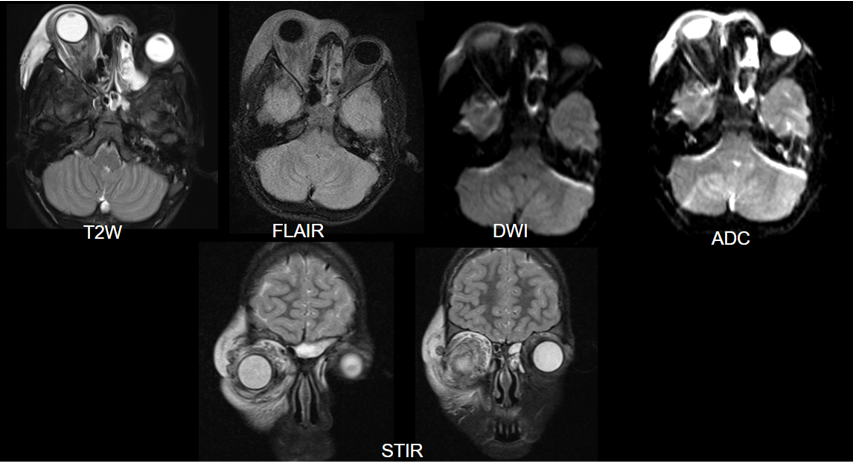

• A large altered signal intensity soft tissue lesion arising from the diaphysis of mid shaft region of humerus in posterior aspect with shallow surface cortical erosions, and spiculated periosteal reaction.

• The lesion demonstrates T2/STIR heterogeneous hyperintense signal and T1 hypointense signal with few cystic spaces. Multiple flow voids noted within lesion ( *). Mild intramedullary edema however no intramedullary extension.